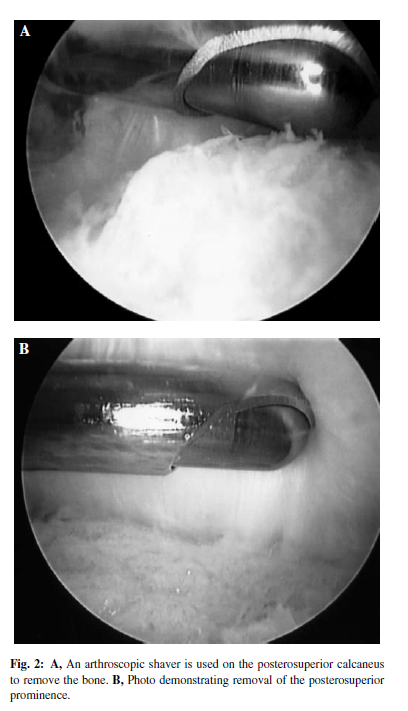

关节镜下手术可以减少并发症、缩短住院时间,病人满意度高,可以在门诊完成。关节镜下手术和中间跟腱劈开入路在手术效果和病人满意度方面无明显差异。

尸体试验:关节镜手术和开放手术对内侧跟腱、跖肌腱和神经的损伤概率无统计学意义。

尸体试验:开放手术比关节镜手术切除跟骨结节更多,清理更完全。